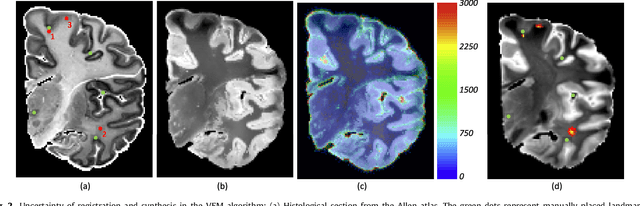

Abstract:Nonlinear registration of 2D histological sections with corresponding slices of MRI data is a critical step of 3D histology reconstruction. This task is difficult due to the large differences in image contrast and resolution, as well as the complex nonrigid distortions produced when sectioning the sample and mounting it on the glass slide. It has been shown in brain MRI registration that better spatial alignment across modalities can be obtained by synthesizing one modality from the other and then using intra-modality registration metrics, rather than by using mutual information (MI) as metric. However, such an approach typically requires a database of aligned images from the two modalities, which is very difficult to obtain for histology/MRI. Here, we overcome this limitation with a probabilistic method that simultaneously solves for registration and synthesis directly on the target images, without any training data. In our model, the MRI slice is assumed to be a contrast-warped, spatially deformed version of the histological section. We use approximate Bayesian inference to iteratively refine the probabilistic estimate of the synthesis and the registration, while accounting for each other's uncertainty. Moreover, manually placed landmarks can be seamlessly integrated in the framework for increased performance. Experiments on a synthetic dataset show that, compared with MI, the proposed method makes it possible to use a much more flexible deformation model in the registration to improve its accuracy, without compromising robustness. Moreover, our framework also exploits information in manually placed landmarks more efficiently than MI, since landmarks inform both synthesis and registration - as opposed to registration alone. Finally, we show qualitative results on the public Allen atlas, in which the proposed method provides a clear improvement over MI based registration.